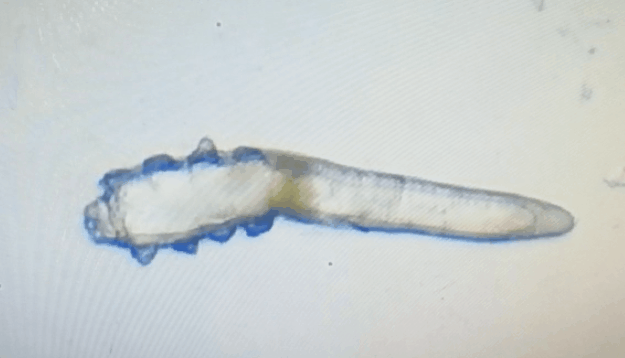

廈門眼科中心眼表及角膜病專家商旭敏博士指出:蠕形螨中的毛囊蠕形螨和皮脂蠕形螨可寄居于人體。在眼部,毛囊蠕形螨常寄居于睫毛囊,而皮脂蠕形螨多寄居于眼瞼皮膚的皮脂腺和瞼板腺。蠕形螨瞼緣炎是蠕形螨感染瞼緣所致的慢性炎性反應性疾病,主要累及瞼緣皮膚、睫毛囊和腺體以及瞼板腺,以眼癢、眼異物感、眼干、瞼緣充血、鱗屑及睫毛根部袖套狀分泌物等為典型臨床表現(xiàn),嚴重者可引起結膜及角膜并發(fā)癥,該病可能具有一定的傳染性。

蠕形螨的危害不容小覷?。?!

蠕形螨會引起睫毛異常,引發(fā)瞼緣炎性反應,瞼板腺堵塞,引起結膜炎、角膜炎等并發(fā)癥,嚴重的話將發(fā)生角膜穿孔致視力損傷甚至失明。